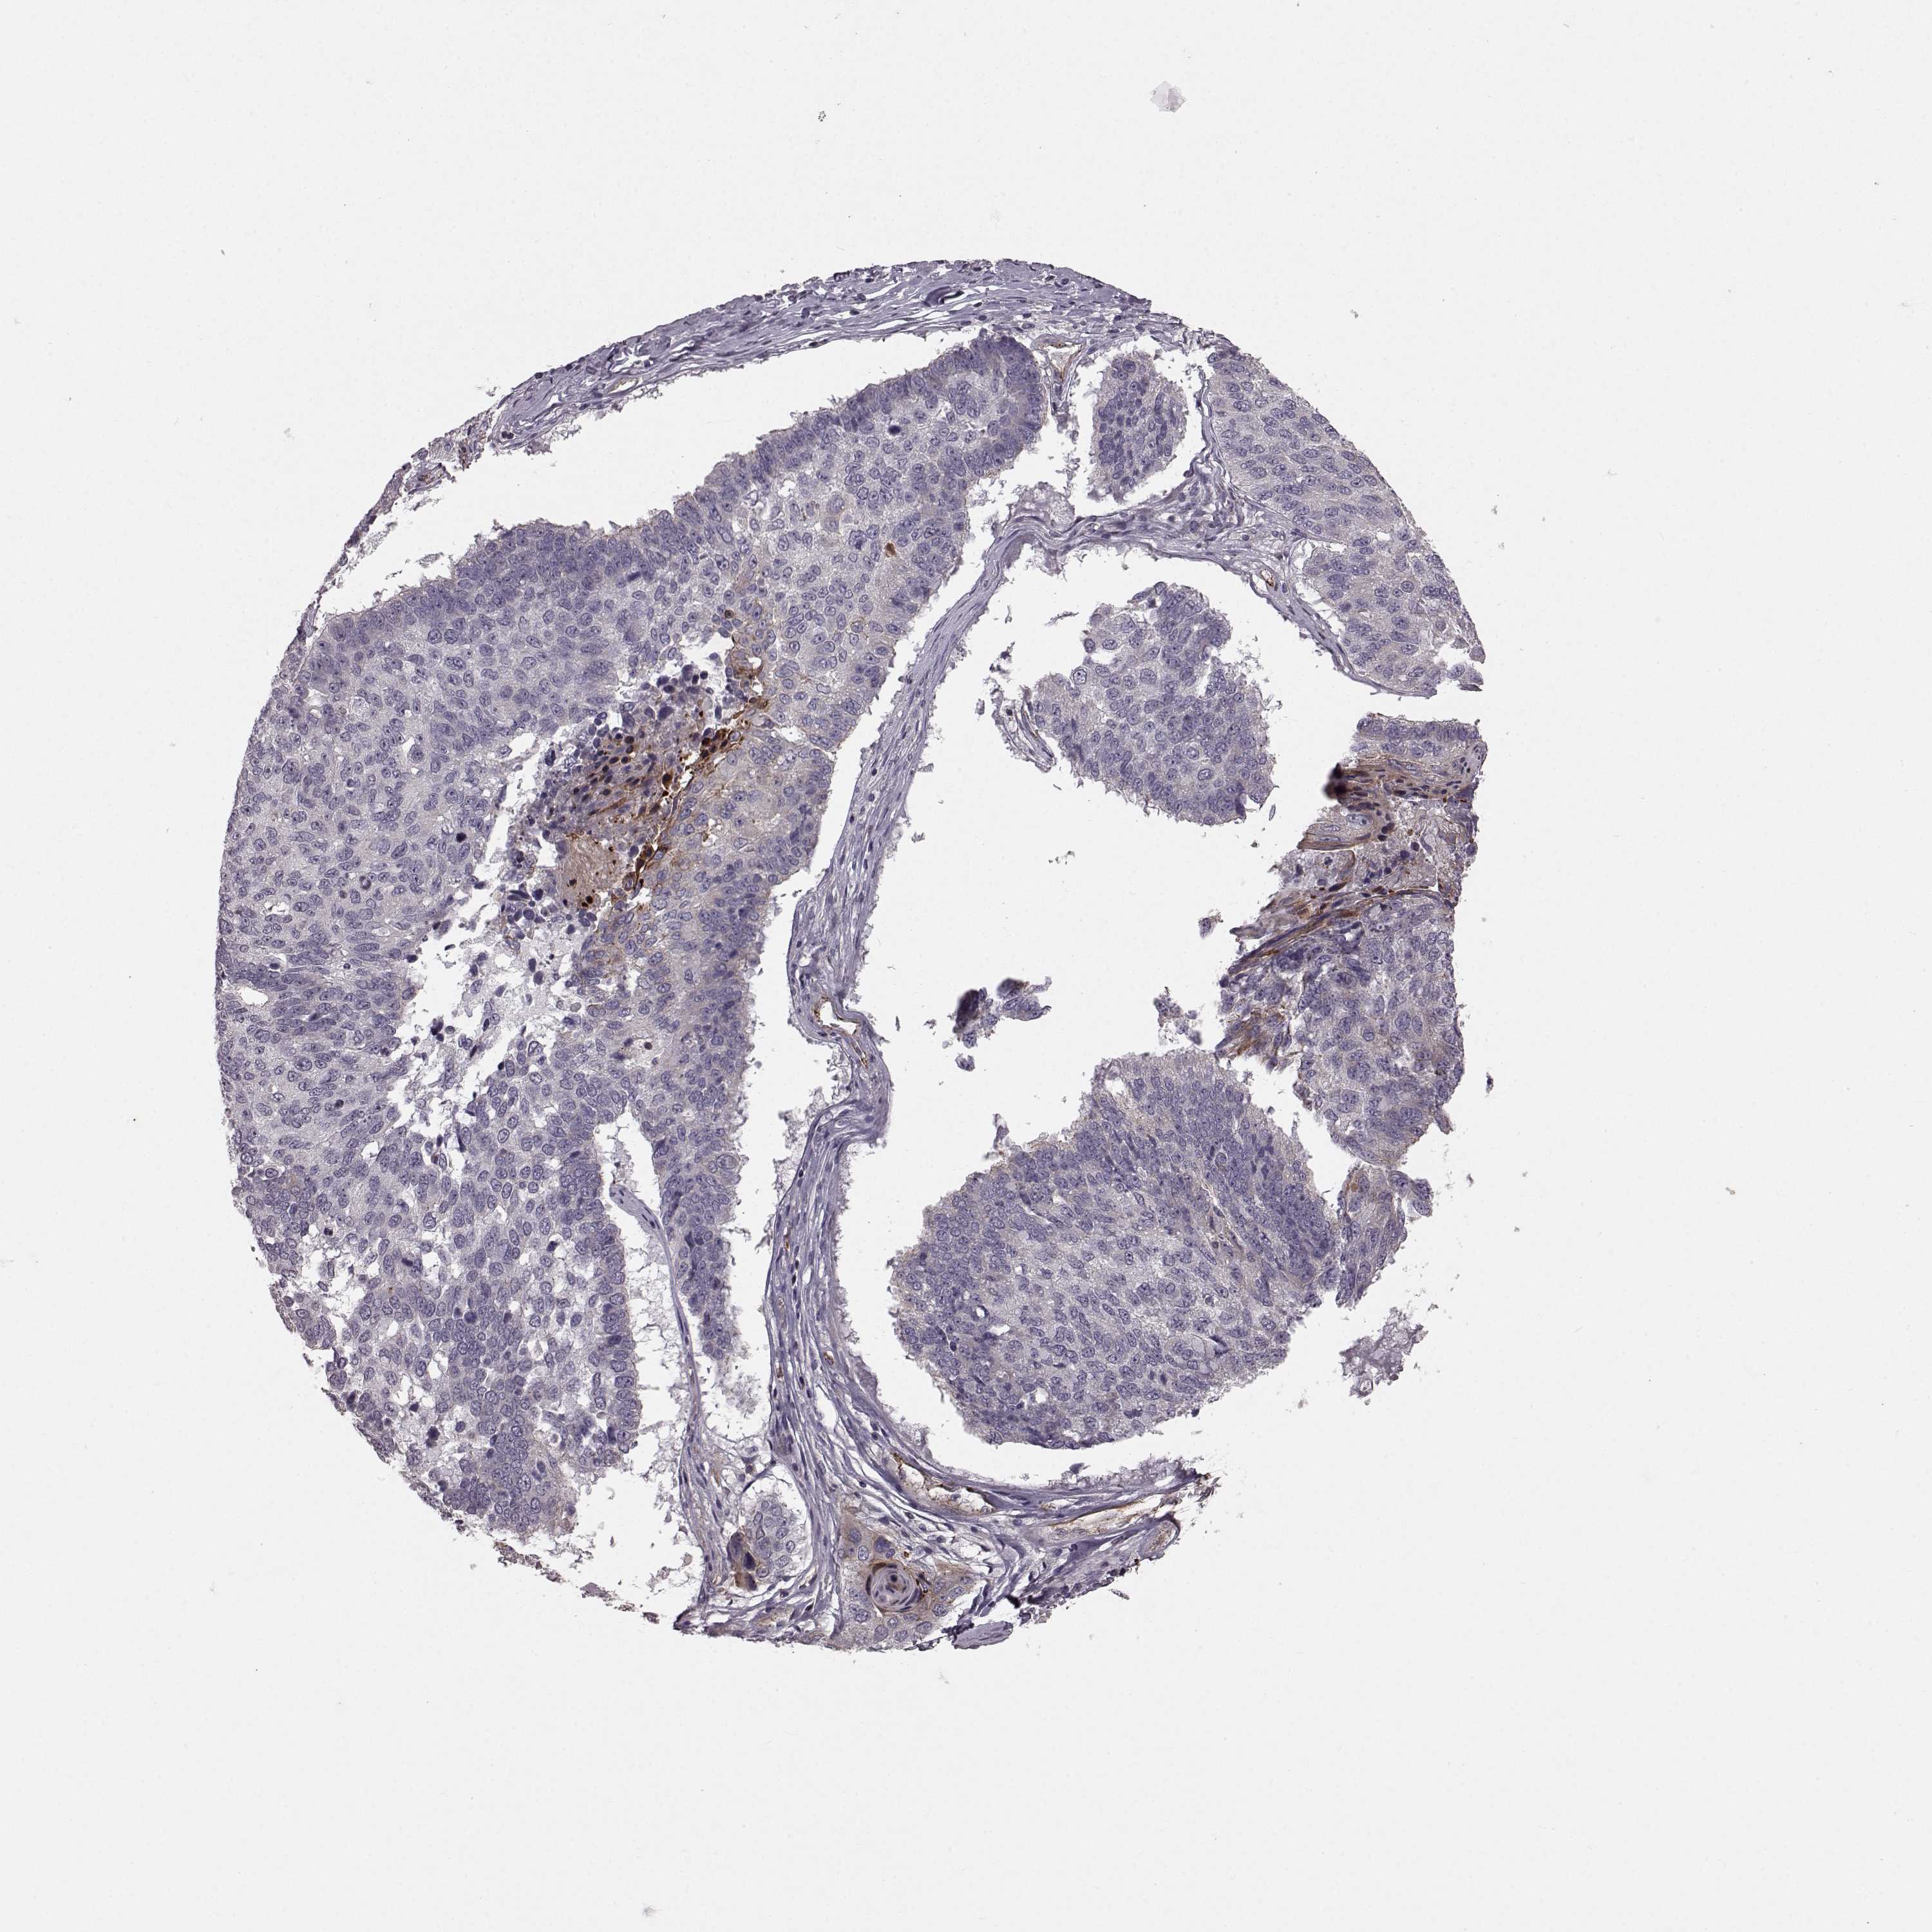

LUNG SQUAMOUS CELL CARCINOMA (TCGA) - Interactive survival scatter ploti

The Survival Scatter plot shows the clinical status (i.e. dead or alive) for all individuals in the patient cohort, based on the same data that underlies the corresponding Kaplan-Meier plots. Patients that are alive at last time for follow-up are shown in blue and patients who have died during the study are shown in red.

The x-axis shows the expression levels (FPKM) of the investigated gene in the tumor tissue at the time of diagnosis. The y-axis shows the follow-up time after diagnosis (years). Both axes are complimented with kernel density curves demonstrating the data density over the axes. The top density plot shows the expression levels (FPKM) distribution among dead (red) and alive patients (blue). The right density plot shows the data density of the survived years of dead patients with high and low expression levels respectively, stratified using the cutoff indicated by the vertical dashed line through the Survival Scatter plot. This cutoff is automatically defined based on the FPKM cutoff that minimizes the p-score. The cutoff can be changed by dragging the vertical line or by entering a cutoff value in the square labeled "Current cut-off".

Under the Survival Scatter plot the p-score landscape (black curve; left axis) is shown together with dead median separation (red curve; right axis). Dead median separation is the difference in median mRNA expression between patients who have died with high and low expression, respectively. It is calculated as follows: median FPKM expression of dead patients with high expression - median FPKM expression of dead patients with low expression. This is intended to aid the user in visually exploring custom cutoffs and the associated p-scores and dead median separation.

Individual patient data is displayed and can be filtered by clicking on one or more of the category buttons on the top of the page. Categories describing expression level and patient information include: high, low, alive, dead, female, male and tumor stages. The scale of the x-axis can be toggled between linear and log-scale by clicking on the "x log" button. Mouse-over function shows TCGA ID, patient information and mRNA expression (FPKM) for each patient.

& Survival analysisi

Kaplan-Meier plots summarize results from analysis of correlation between mRNA expression level and patient survival. Patients were divided based on level of expression into one of the two groups "low" (under cut off) or "high" (over cut off). X-axis shows time for survival (years) and y-axis shows the probability of survival, where 1.0 corresponds to 100 percent.

SLC22A18 is not prognostic in Lung Squamous Cell Carcinoma (TCGA)

Best expression cut offi

Based on the FPKM value of each gene, patients were classified into two groups and association between prognosis (survival) and gene expression (FPKM) was examined. The best expression cut-off refers the FPKM value that yields maximal difference with regard to survival between the two groups at the lowest log-rank P-value. Best expression cut-off was selected based on survival analysis .

When clicking on this number, the vertical dashed line indicating cut-off, the interactive survival plot, and the Kaplan-Meier curve will be adjusted to show results based on the best expression cut-off.

: 3.82

P scorei

Log-rank P value for Kaplan-Meier plot showing results from analysis of correlation between mRNA expression level and patient survival.

N/A

TCGA RNA samplesi

RNA-seq data is reported as average FPKM (number Fragments Per Kilobase of exon per Million reads), generated by the The Cancer Genome Atlas (TCGA) .

Normal distribution across the dataset is visualized with box plots, shown as median and 25th and 75th percentiles. Points are displayed as outliers if they are above or below 1.5 times the interquartile range. FPKM values of the individual samples are presented next to the box plot.

Average pTPM 9.5

Number of samples 489